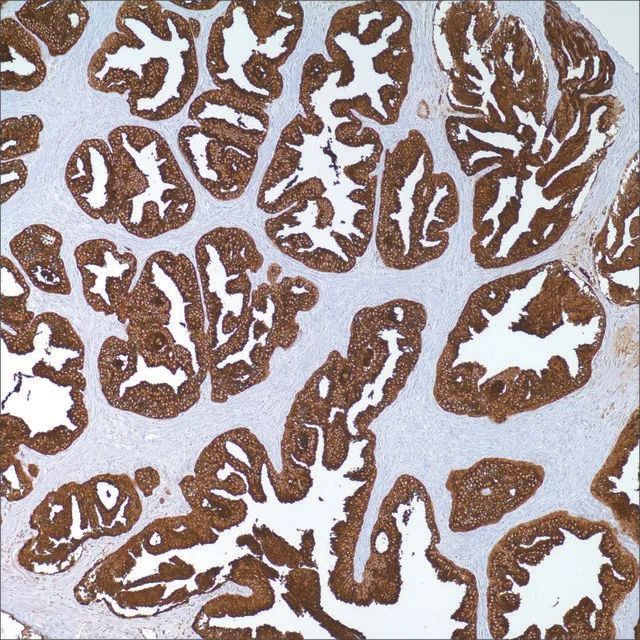

Blastic plasmacytoid dendritic cell neoplasm (BPDCN), previously known as CD4+/CD56+ hematodermic neoplasm or blastic NK-cell lymphoma, is a malignant neoplasm composed of immature hematopoietic precursors of plasmacytoid dendritic cells. The most frequent manifestation is a skin lesion, bone marrow involvement, and regional lymphadenopathy. Myeloid leukemia cutis (LC), myeloid sarcoma, and large aggressive B cell lymphomas should be differentiated from BPDCN. Recently, it has been reported that these entities can be distinguished by using immunohistochemistry (IHC) in paraffin-embedded tissue sections. In this study, 23 myeloid LC and 12 BPDCN cases were evaluated using a panel of antibodies against CD123, TCL1, CD4, CD56, MPO and CD33; with results as follows: anti-CD123 stained 4 cases (17%) of myeloid LC and 10 cases (83%) of BPDCN; anti-TCL-1 stained 2 cases (9%) of myeloid LC and 9 (82%) of 11 cases of BPDCN; anti-CD4 stained 2 cases (9%) of LC and all 12 cases (100%) of BPDCN; anti-CD56 stained 12 cases (52%) of LC and all 12 cases (100%) of BPDCN; anti-myeloperoxidase stained 7 cases (30%) of LC and 0 cases (0%) of BPDCN. Anti-CD33 was not helpful; it stained 18 (78%) cases of LC and 11 cases (92%) of BPDCN. The results indicated that a panel that includes antibodies against CD4, CD56, CD123, and TCL-1 can appropriately distinguish between myeloid LC and BPDCN.

CD123 Positive Control Slides, Product No. 198S, are available for immunohistochemistry (formalin-fixed, paraffin-embedded sections).

technique(s) immunohistochemistry (formalin-fixed, paraffin-embedded sections): 1:25-1:100

控制 blastic plasmacytoid dendritic cell neoplasm